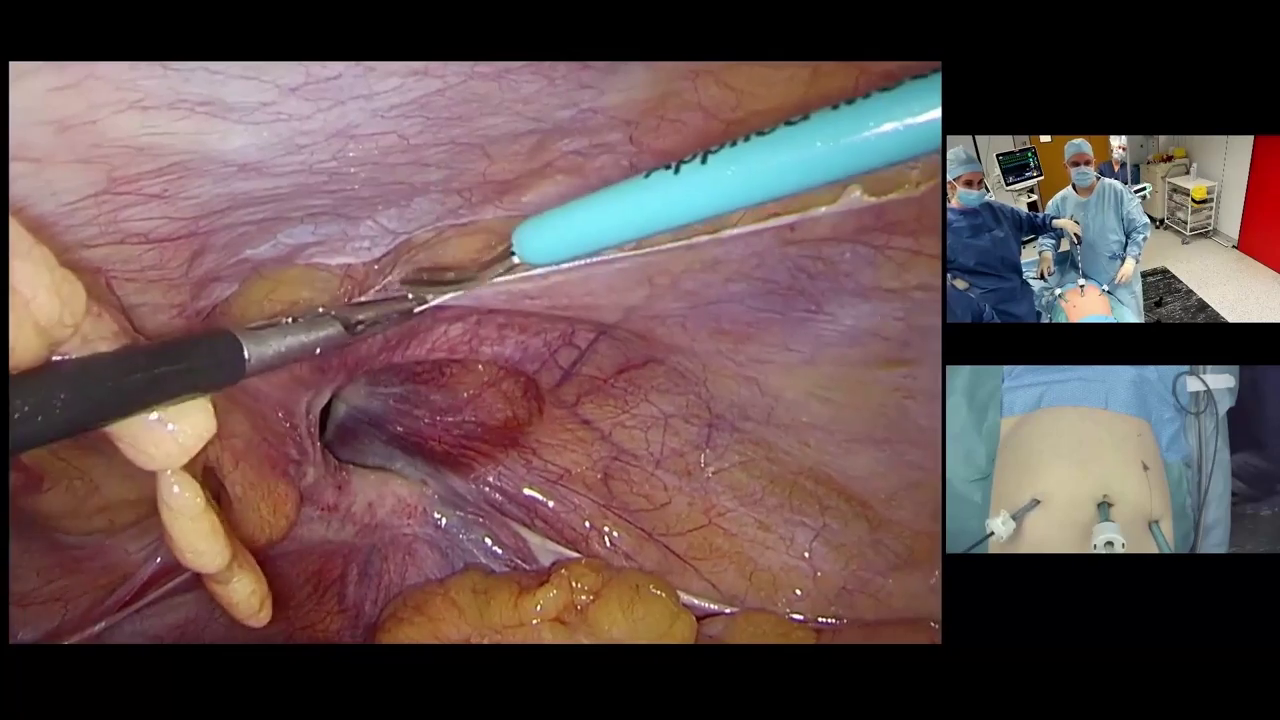

Dr. Malcher | Robotic repair of incarcerated inguinal hernia using CO2 asperation tip

Doctor(s): Dr. Malcher Description of of the case: Robotic repair of incarcerated inguinal hernia using CO2 asperation tip Products Used: Ventralight™ ST Mesh [...]